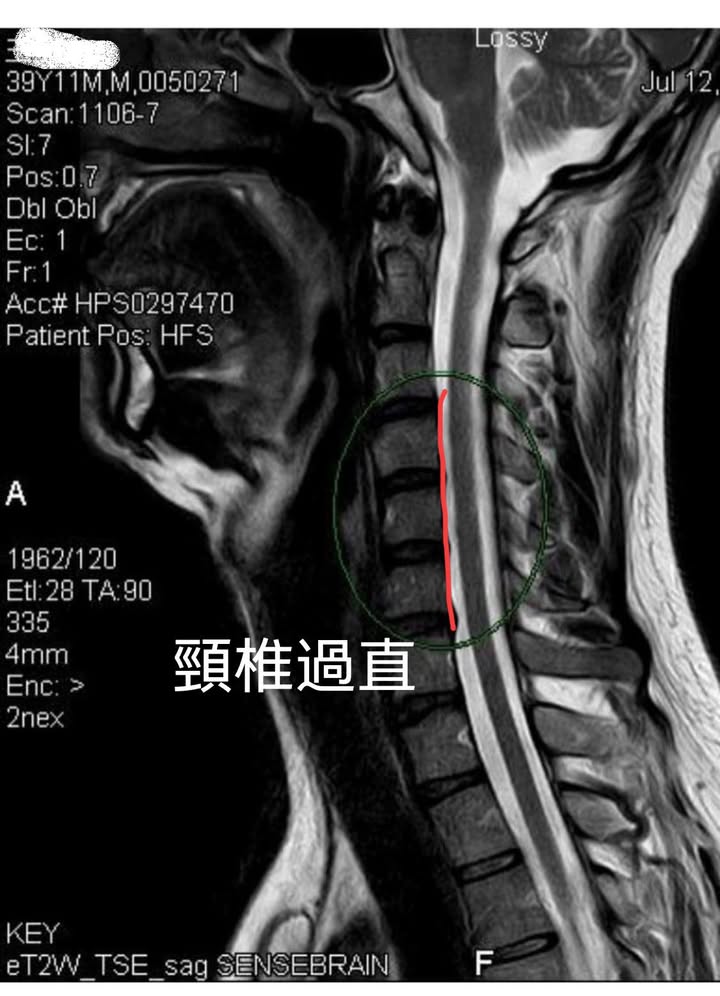

Cervical Spine Treatment Cases 頸椎治療案例 頸椎壓迫竟導致自律神經失調?耳鳴、心悸、暴瘦全因筋膜失衡! 2021.02.18 頸椎壓迫神經根導致工作受限?非手術微創療法改善關鍵公開 2021.02.17 頸椎脊髓壓迫五大症狀公開!你也有雙腳沉重、手腳麻電感嗎? 2021.01.15 長期頭痛吃藥沒效?小心你可能是「頸源性頭痛」患者 2021.01.07 #感謝新北市蘆洲區楊先生熱情見證 #頸椎病變引起肩膀痠痛無法睡眠 #曾經大痛到想立刻... 2020.12.31 #感謝新北三重劉小姐熱情見證 #神經根型頸椎病經典案例 #曾經手麻痛到無法騎摩托車 #... 2020.12.25 #遠從台東縣的熱情見證 #五個多小時的車程三百多公里很辛苦 #疼痛超過兩年打過頸椎三... 2020.12.24 #頸椎酸痛到無法睡覺是怎們回事 #醫學中心證實頸椎間盤突出 #神外醫師建議開刀但患者... 2020.12.19 #頸椎曲線弧度非常重要 #頸椎嚴重壓迫有可能逆轉嗎 #肩膀疼痛到不行合併走路都無力 #... 2020.12.09 頸椎退化壓迫神經根怎麼辦?大直林小姐四週見效的中醫微創療法 2020.12.08 #特殊案例長年過敏性鼻炎 #起因居然是頸椎交感神經筋膜壓迫 #打開椎動脈循環🔄找到解... 2020.12.05 #恭喜新店陳小姐頸椎療程畢業 #神經根型卡壓醫案 #頸椎整合中醫微創療法逆轉勝 #告別... 2020.11.24 #特殊案例頸椎手術後又再度突出案例 #感謝台中劉大哥熱情見證 #親自手捏醫師娃娃公仔... 2020.11.18 #頸椎病居然會導致手快速萎縮 #脊髓型頸椎病案例 #感謝高雄王大哥熱情見證 #頸椎整合... 2020.11.13 #神經根型頸椎病讓人痛到無法入眠 #感謝新店陳小姐熱情見證 #患者的疼痛日誌讓人感動 ... 2020.11.11 ← 上一頁 3 4 5 6 7 下一頁 →